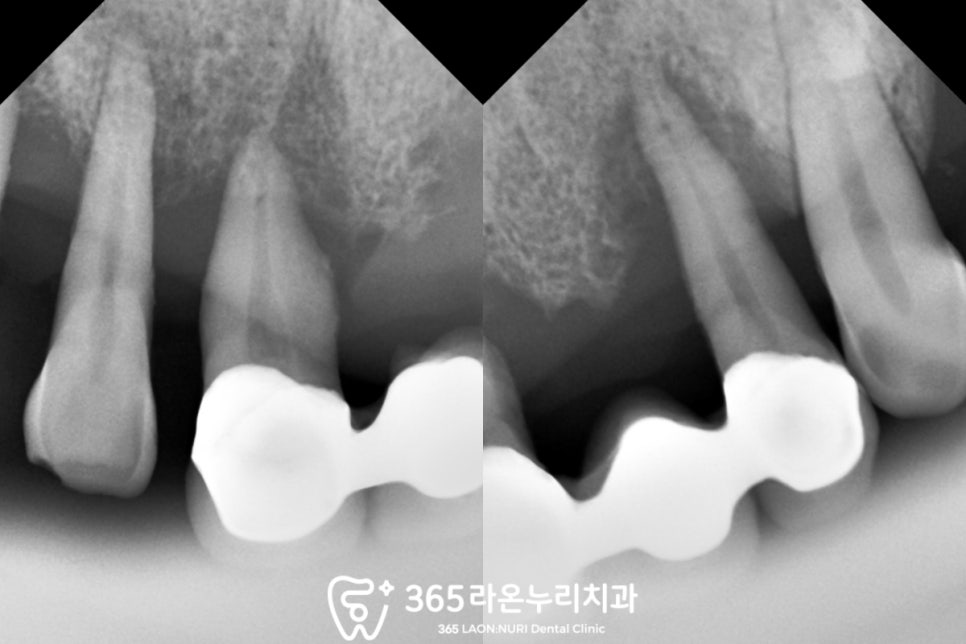

다시 본론으로 돌아와

픽스처와 뼈가 잘 결합되었다면

어버트먼트를 연결합니다.

그리고 이 위로

임시치아를 올려드리게 되는데

하루아침에 어금니가 생기면

당연히 남의 이 같다 느끼실 수 있기에

여러 번 조정과 제작을 해드렸었답니다.^^